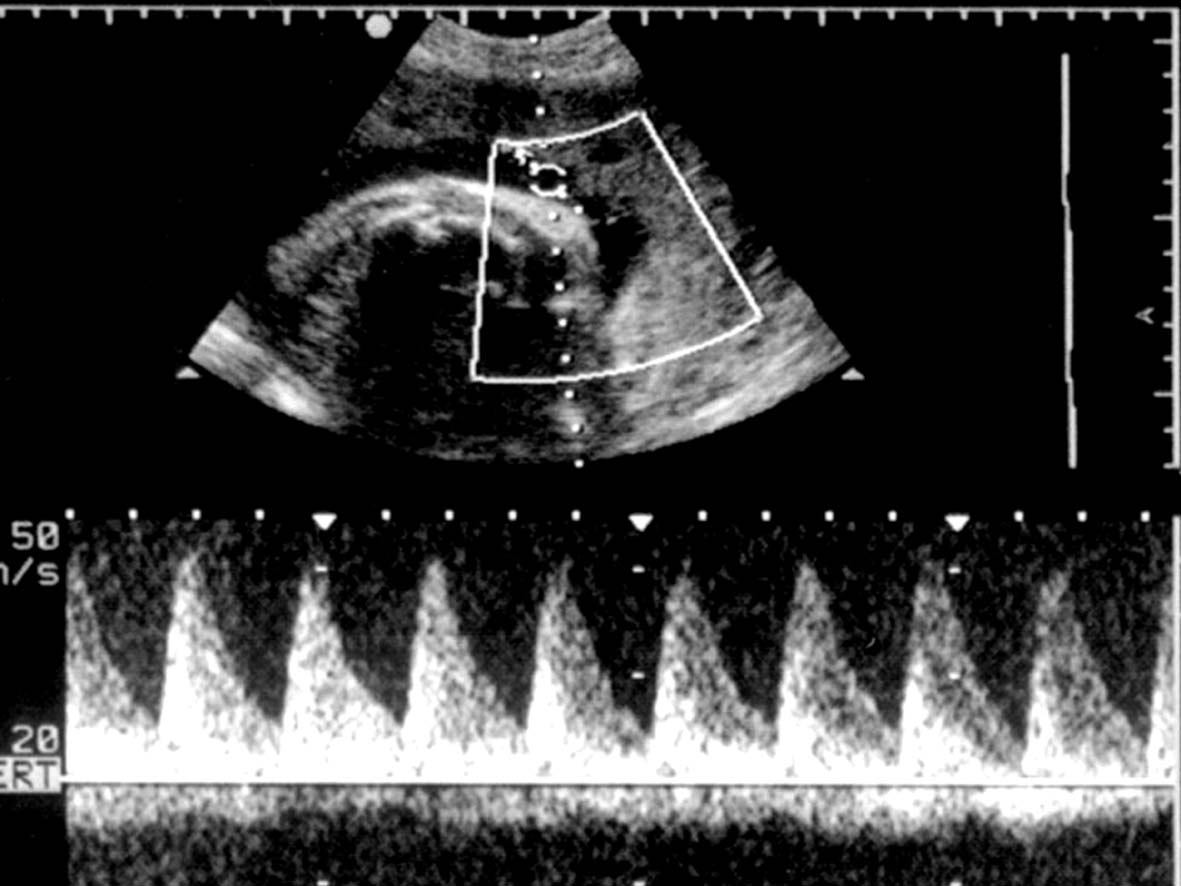

3.超声多普勒血流显像 在超声显像的引导下启动彩色多普勒血流显像可以在压迹表面直接显示脐带的血流图像(图1B)。显示两色、三条血管时至少有绕颈一圈,如果显示两色、能分辨至少四条以上血管即提示绕颈多于一圈;横切面可显示环绕颈部的脐带血流(图1C)。绕颈的脐带内血流速度较快、阻力增高(图2),其他部位的脐带内血流多无异常改变。如果发现非绕颈部位脐动脉血流异常时,尤其是S/D大于3.0时,应及时提示临床积极处理,避免严重的胎儿宫内窘迫发生。

图2脐带绕颈脐动脉血流速度曲线